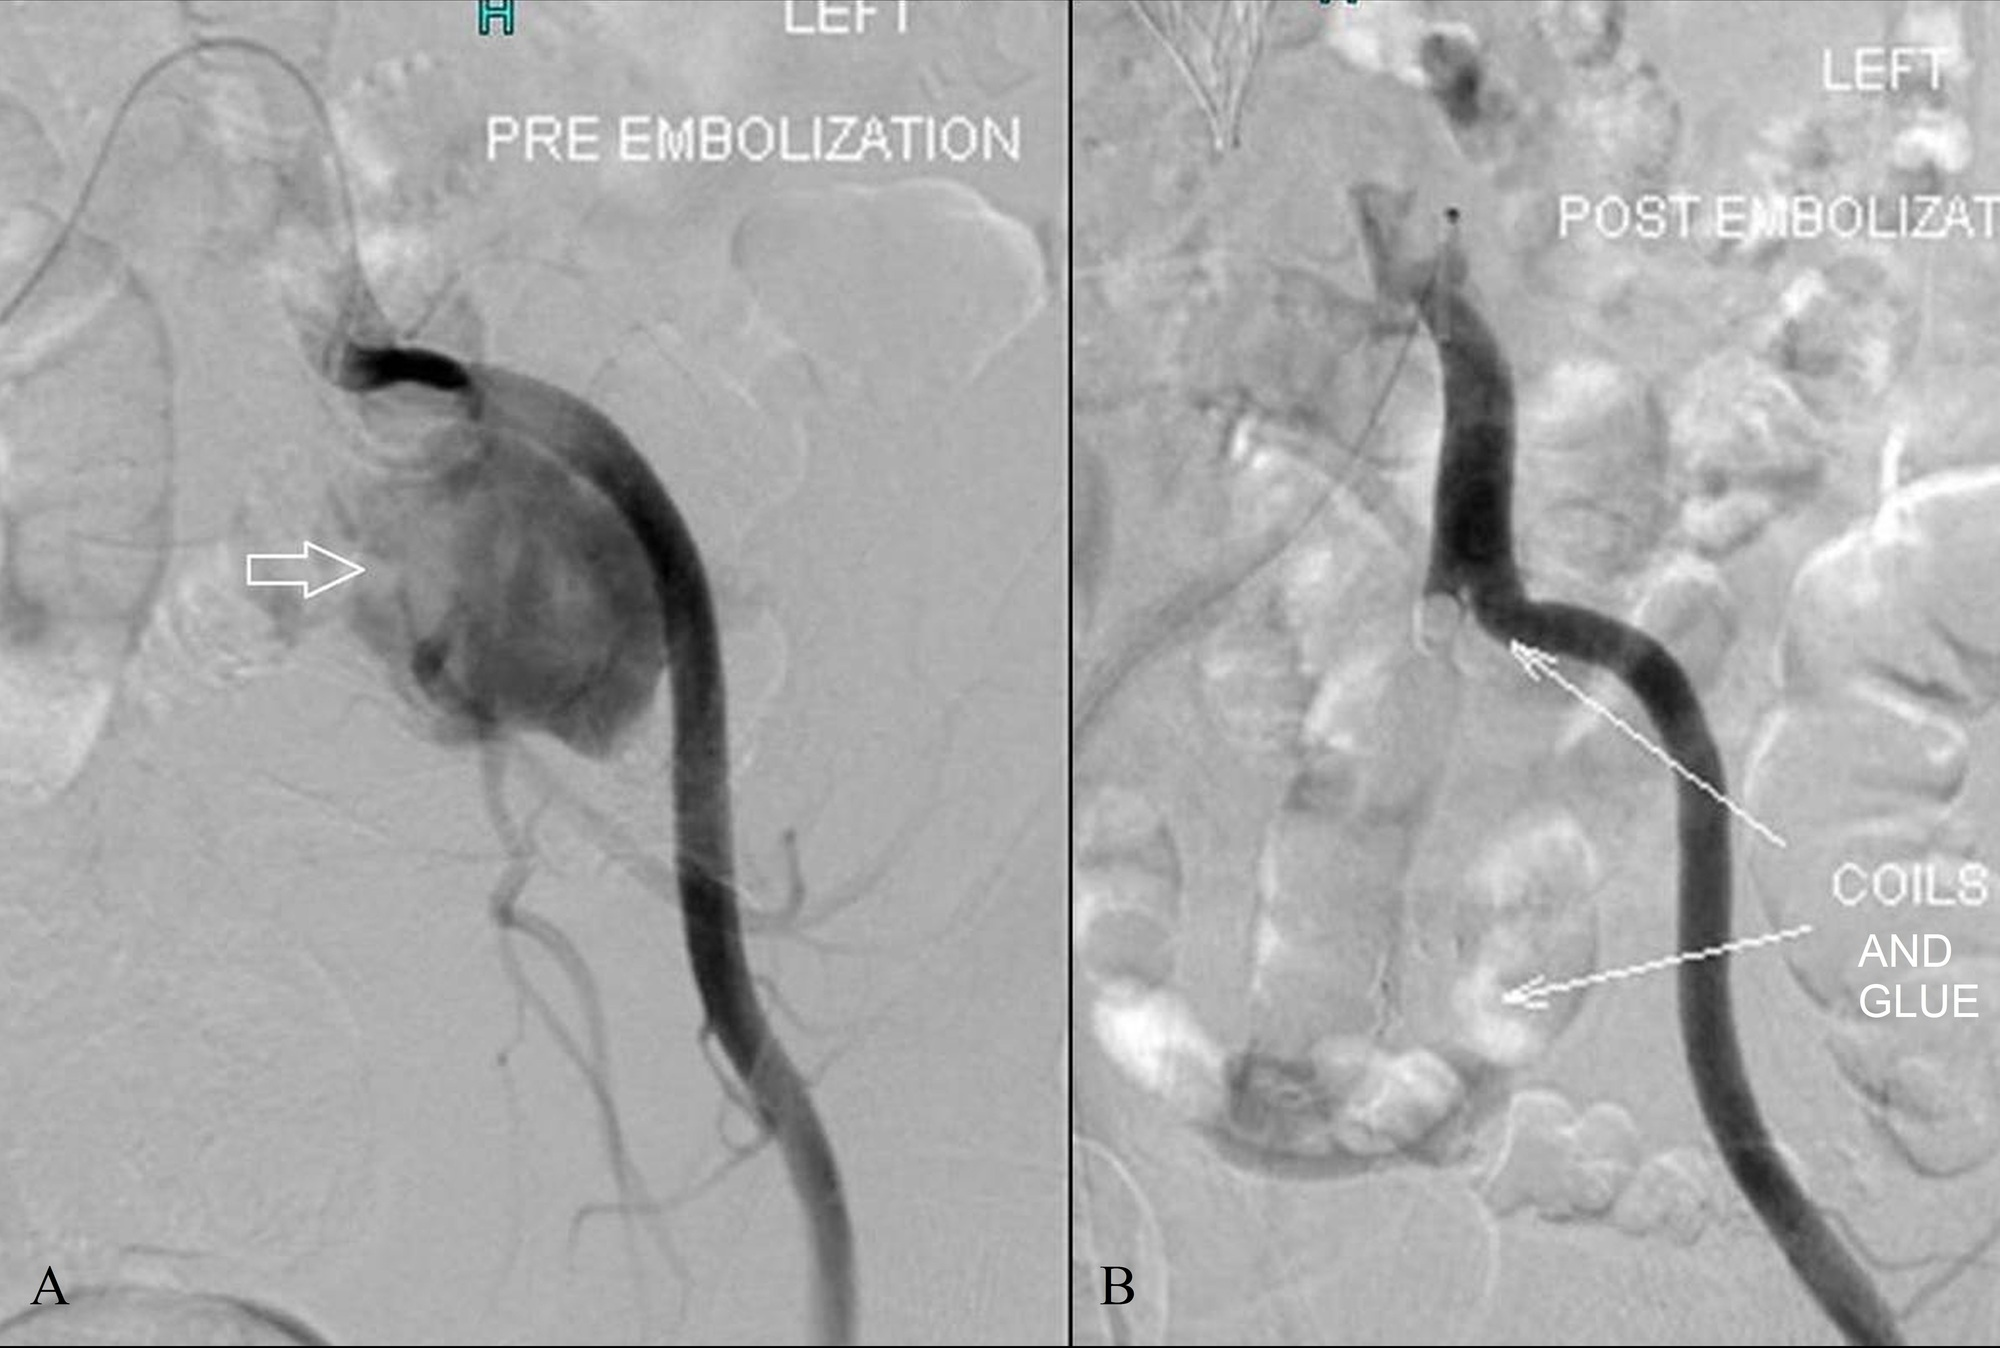

From www.researchgate.net

Angiogram of the left deep circumflex artery after glue embolization Embolization Glue Embolization, gelfoam, coils, glue, onyx, polyvinyl alcohol, embosphere therapeutic embolization is the intentional. technique of glue embolization. embolization is defined as the therapeutic introduction of various substances into the circulation to occlude vessels, either to arrest or. endovascular embolization is an effective treatment option for cerebral arteriovenous malformations (avms) and. nontarget vascular occlusion via inadvertent embolization. Embolization Glue.